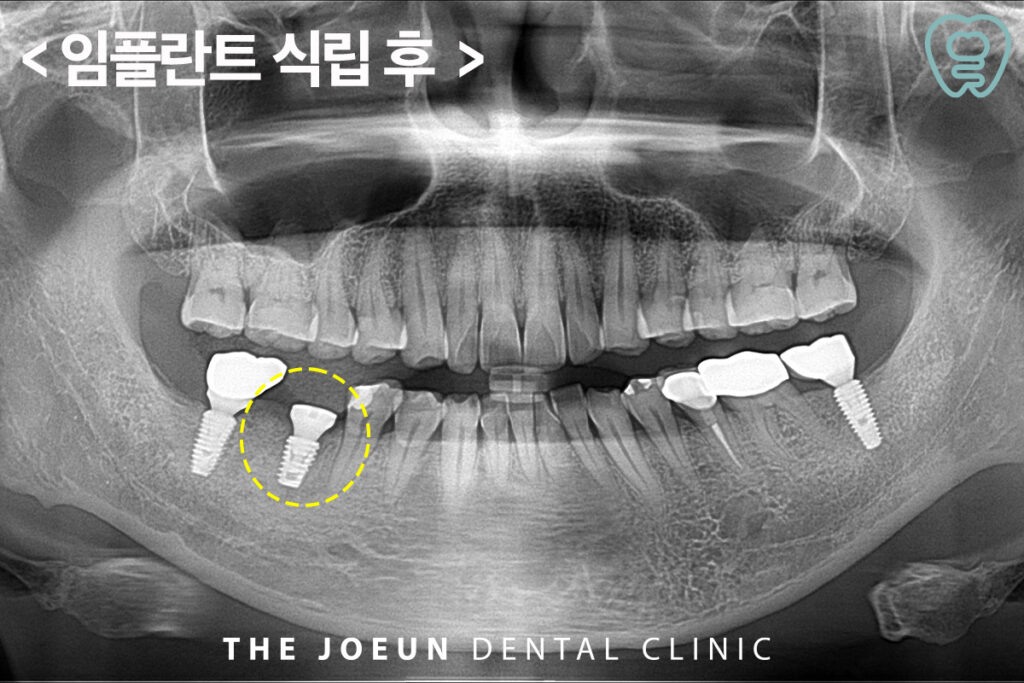

6개월 뒤 임플란트 식립을 진행하였습니다. 임플란트는 치조골에 인공 치근을 식립하는 방식이므로 골조직이 튼튼해야만 안정적으로 고정이 되는 것이 기본으로 성공의 핵심은 골유착에 있다고 해도 과언이 아닌데요. 골유착이란 뼈와 임플란트가 단단히 결합해 씹는 기능을 무리 없이 수행할 수 있을 만큼 안정적으로 고정되는 상태를 말합니다. 골유착이 제대로 이루어져야 임플란트의 수명이 길어지고 일상 속 불편함도 줄일 수 있습니다.

이어서 최종 보철물까지 마무리를 하였습니다.